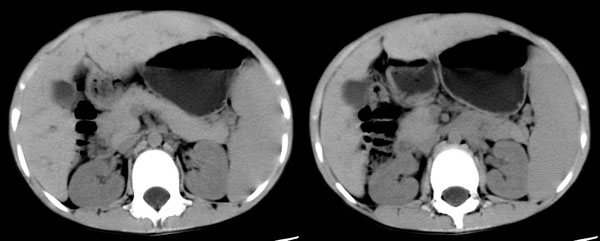

右股动脉穿刺,将导管置入脾动脉远端,造影显示脾明显增大,脾静脉、门静脉未见异常,采用明胶海绵颗粒行脾动脉部分栓塞。

栓塞后造影可见部分脾动脉分支消失,栓塞面积大于50%。

随访:患者术前白细胞2000,血小板7万/l,术后3周复查,白细胞升至9000,血小板升至17万/l,治疗效果满意。